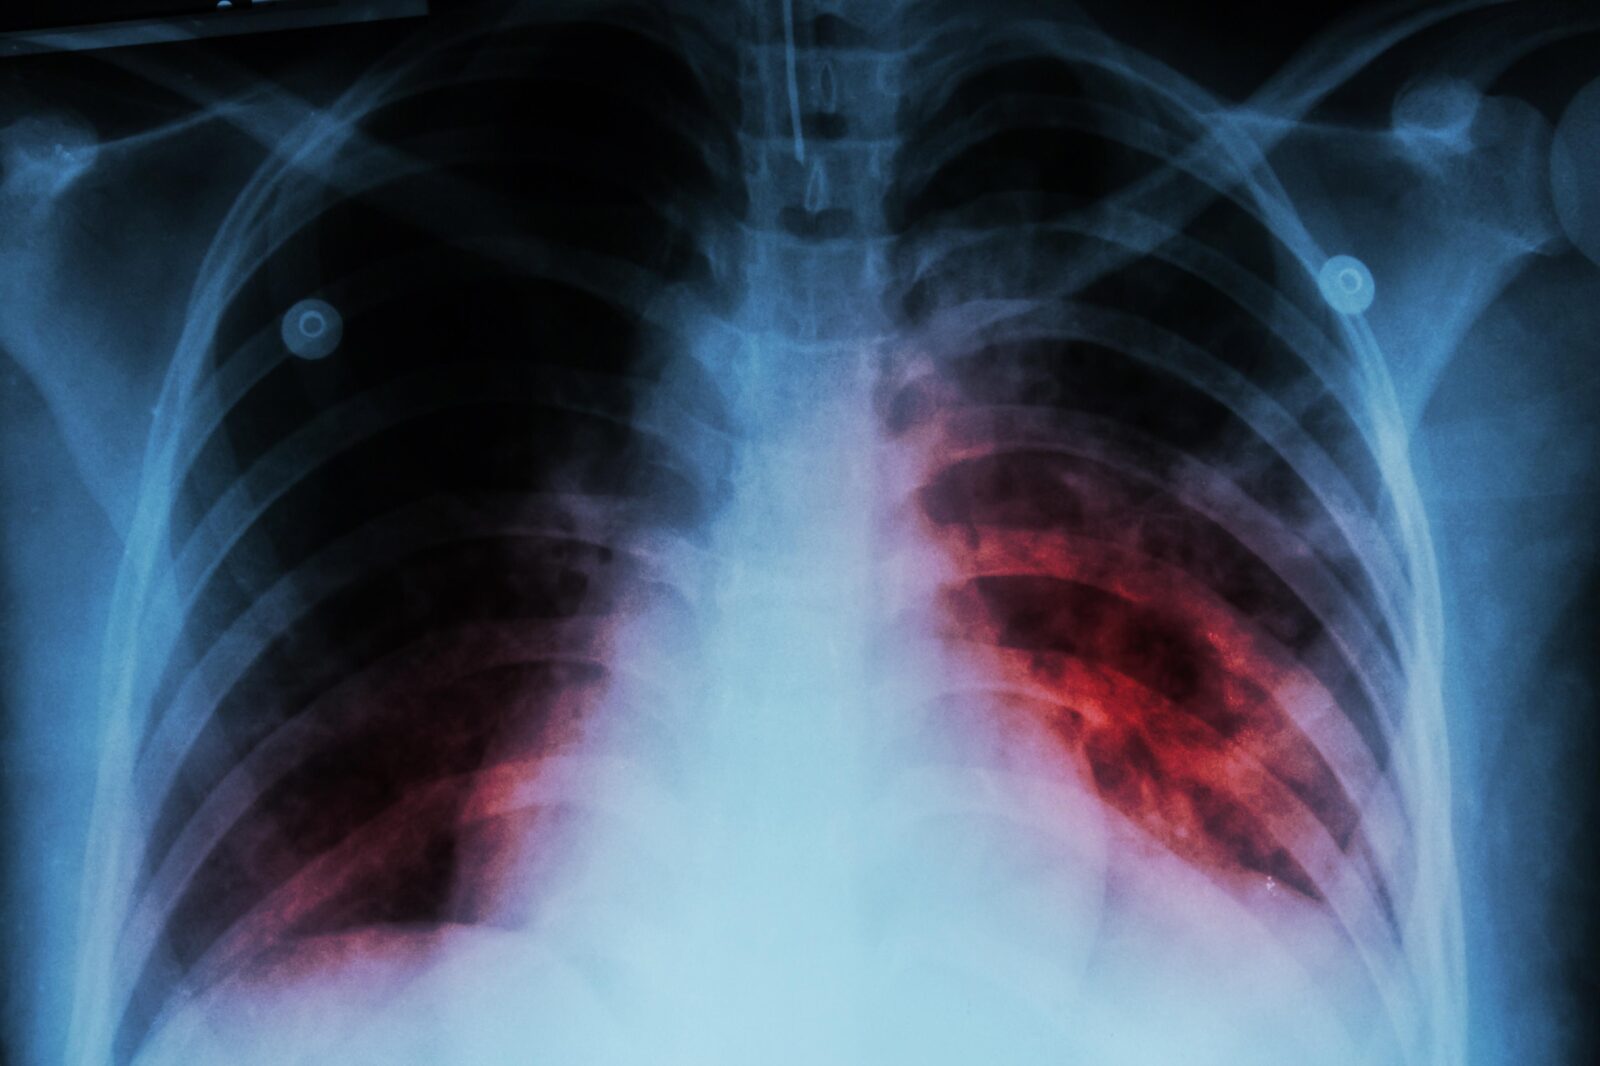

El 24 de marzo se conmemora el Día Mundial de la prevención contra la Tuberculosis, enfermedad que es curable si se detecta a tiempo

“La tuberculosis se transmite a través de la saliva cuando hablamos, cantamos, reímos y tosemos, ya que despedimos una gran cantidad de saliva, y si el paciente se encuentra infectado puede trasmitir a esta enfermedad a través de las gotitas de la saliva; este al afecta los pulmones”, señaló.

Mencionó que los síntomas son, fiebre, descenso de peso, tos de más de quince días, por ello, si la tos dura más de quince días, el paciente se debe hacer una detección a través de la baciliscopia, un estudio de la flema, la cual se detecta los bacilos que produce la tuberculosis.